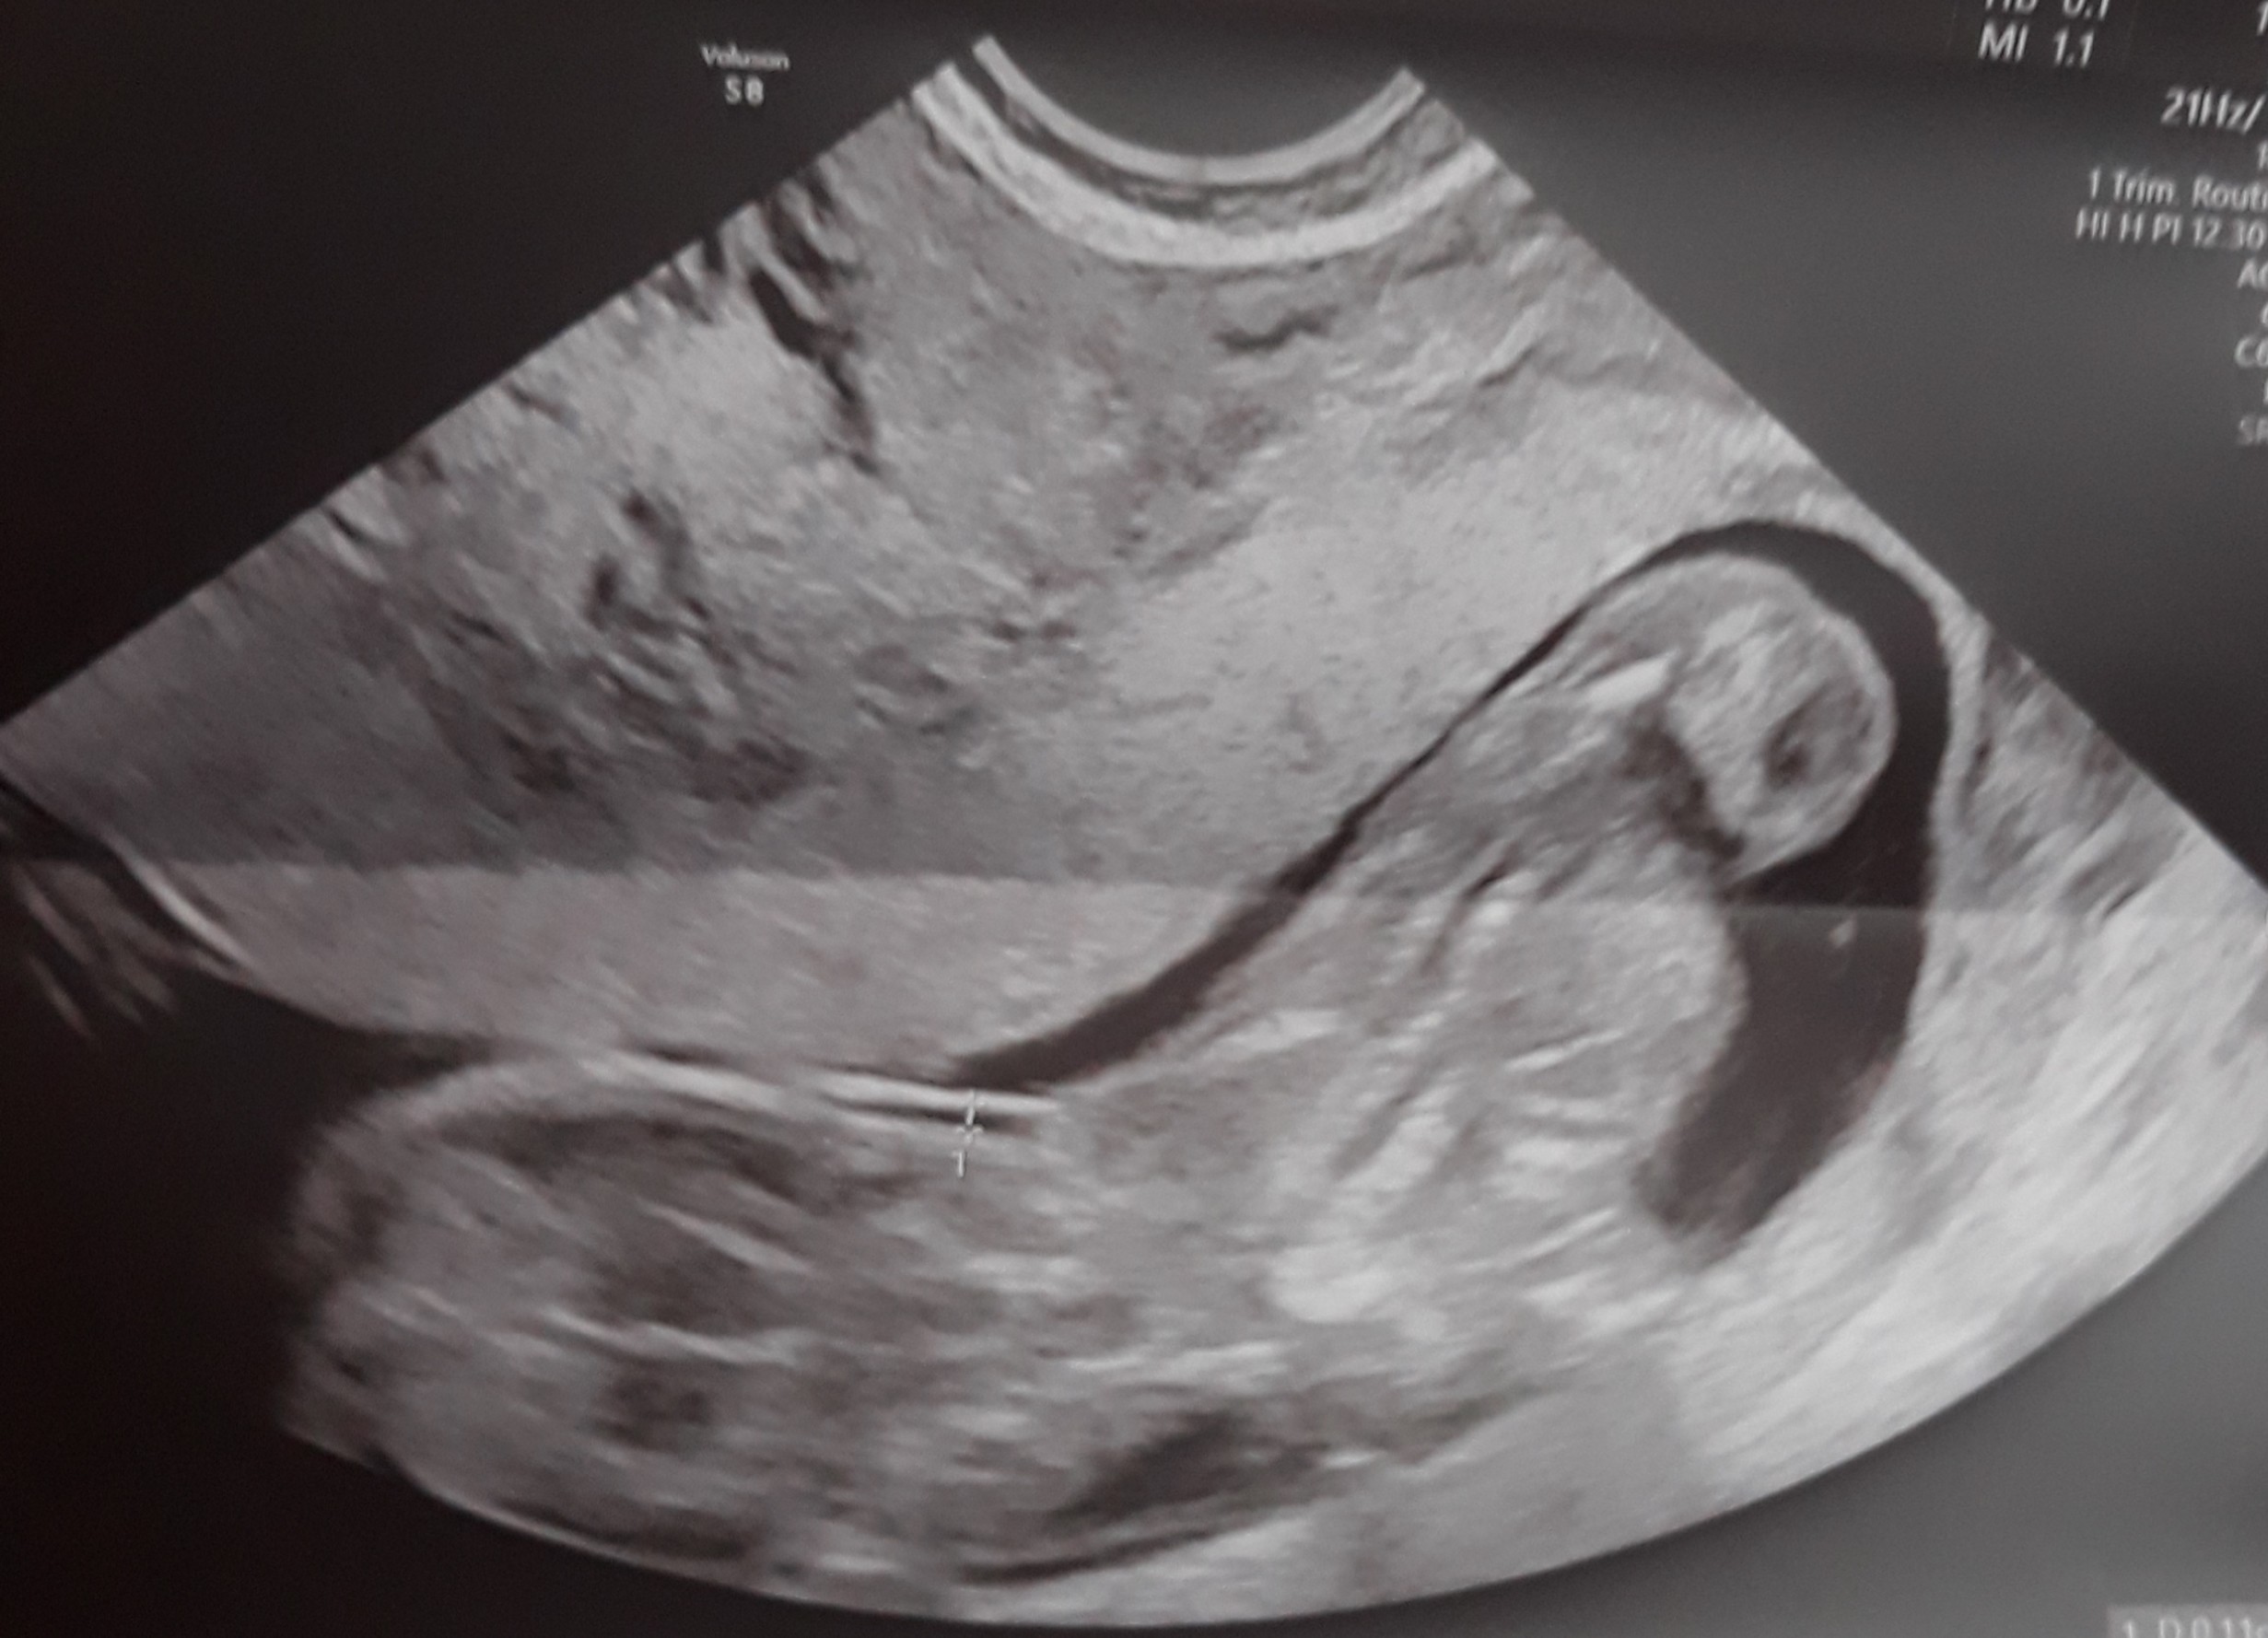

Usg w 13 tc

Witam , wiem , że to może głupie pytanie , ale to moja 1 ciąża i się wszystkim przejmuję. Dlaczego te usg jest takie dziwne , zamazane ? Wogóle nie widać kształtów dziecka. Czy któras też tak miała?

Tylko takie zdjęcie masz ? Wygląda trochę jakby była próba łapania przezierności, ale dziwnie nie bokiem tylko tyłem, to drugie chyba jest z pomiarem crl i wygląda na pierwszy rzut oka lepiej, ale też bez szału. Dzidzuś się mocno ruszał? Słabe to zdjęcie, a to ważne usg, masz opis taki porządny ze wszystkimi pomiarami itd.? Jak nie to może powtórz u kogoś z lepszym sprzętem...